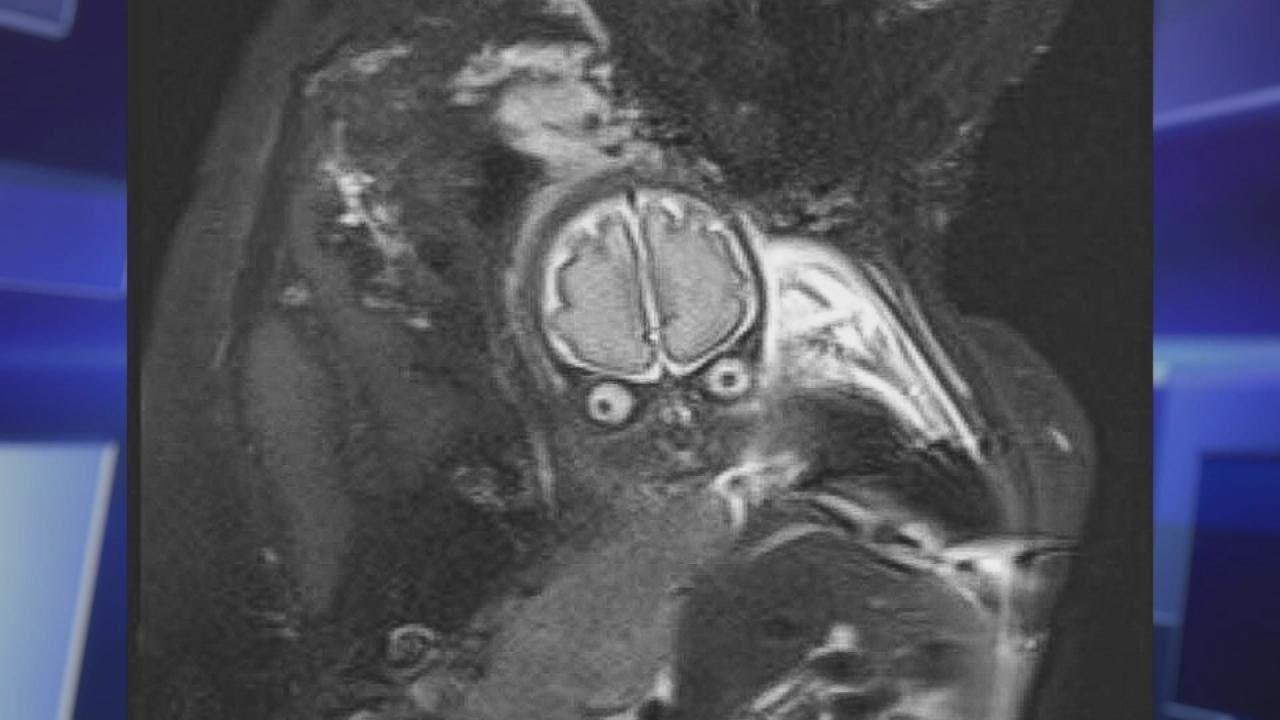

Budući roditelji su ostali pomalo šokirani nakon što su vidjeli rezultate magnetske rezonance koju su naručili doktori. Htjeli provjeriti je li sve u redu s razvojem djeteta, a slika je začudila roditelje jer je njihova beba izgledala kao mali vanzemaljac koji ih gleda na pomalo jeziv način.

S bebom je sve bilo u redu. Kasnije je rođena živa i zdrava, no roditelji će ovu sliku još dugo pamtiti. :)